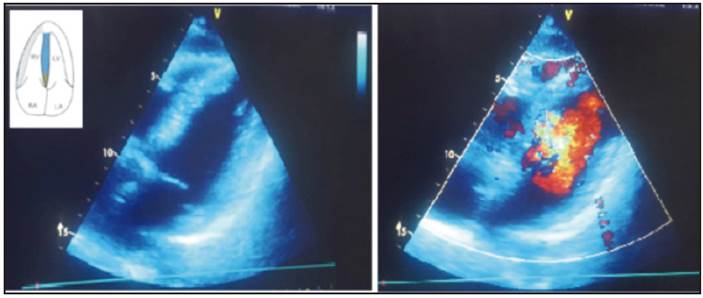

The patient's medical history on admission established the suspicion of takotsubo cardiomyopathy. However, given the risk of a critical coronary lesion, standard care measures for patients with a probable acute coronary syndrome with elevated ST were begun in the emergency room. The institution where she was seen had immediate availability of an angiography, and the percutaneous coro nary intervention showed findings suggestive of takotsubo. She was observed for 24 hours in an intensive care unit due to her frankly reduced ejection fraction (35%) and risk of secondary hemodynamic complications. She was treated with low-dose selective beta blockers, angiotensin receptor antagonists (since she had been taking these to treat her hypertension), an aldosterone antagonist diuretic, acetyl-salicylic acid, an anxiolytic and a lipid lowering medica tion. The pain disappeared when the anxiety resolved, and the patient was subsequently asymptomatic during 48 hours of follow up on the hospital floor. The patient was discharged with an order to continue the hospital treatment and have outpatient follow up and a follow up echocardiogram. Three months after the event, the patient was still asymptomatic on outpatient follow up visits and her echocardiogram showed apical contractility changes with complete recovery of mobility in this zone, an in creased ejection fraction to 60% and disappearance of the left ventricular apical systolic ballooning seen during the acute phase (Figure 3). She was given an order to continue treatment just with the beta-adrenergic blocker due to the risk of relapse in the context of a depressed patient and to continue with antihypertensive treatment, and has had no further complications or new events.